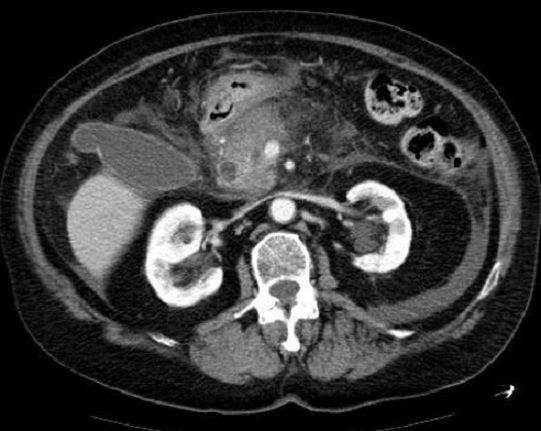

Image radiologique de

pancreatite forme necrotique hemorrhagique avec

aspect des foyer de necrose parenchymateuse

hypodense et defaut de rehaussement ( fleche rouge )

. Image radiologique TDM phase veineuse |